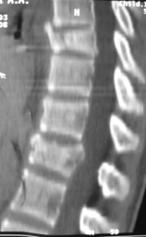

Рис. 12. КТ и рентгенограммы пациента А. 15 лет. Взрывной перелом Th9, Th12. Компрессионный перелом Th10.

А, Б – КТ до операции; В, Г – рентгенограмма после дорсальной непрямой репозиции, фиксации и заднего локального спондилодеза |